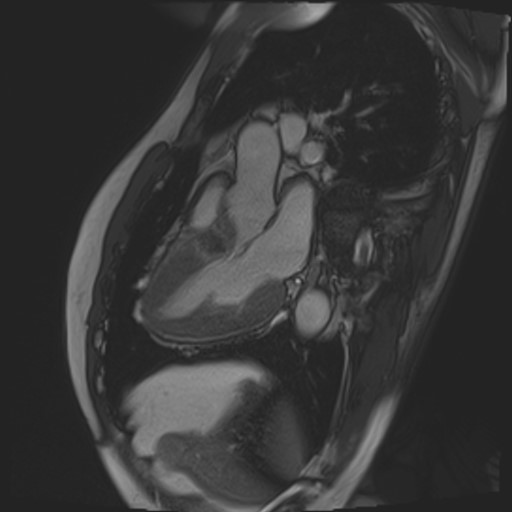

閉塞性肥大型心筋症の心臓に経皮的中隔心筋焼灼術 (PTSMA)を施した画像ですが、MRIでは造影剤を用いる事なく心臓の動きを捉えることができるだけでなく、エタノールにより壊死させた中隔心筋を明瞭に描画することができるので治療効果の判定に有用です。

PTSMA後